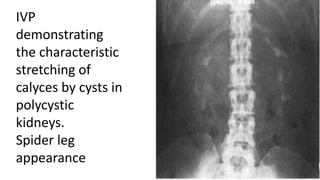

IVP

demonstrating

the characteristic

stretching of

calyces by cysts in

polycystic

kidneys.

Spider leg

appearance

IVP demonstrating the characteristic stretching of calycesby cysts in polycystic kidneys. Spider leg appearance